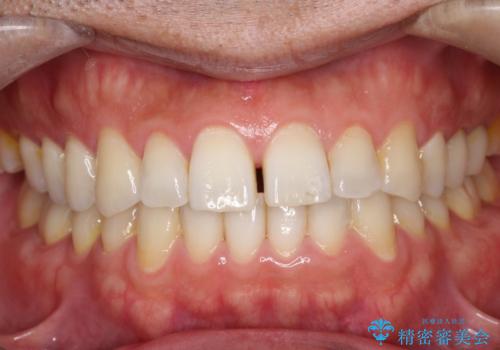

【埋伏歯】犬歯の牽引を行った矯正歯科治療

- 八重歯を主訴に来院されました。

左側犬歯が埋伏していましたが、第一小臼歯(4番目の歯)を抜歯したことでできたスペースに牽引し、右側の飛び出した八重歯を含め、歯全体を整列することができ患者様も満足していただきました。